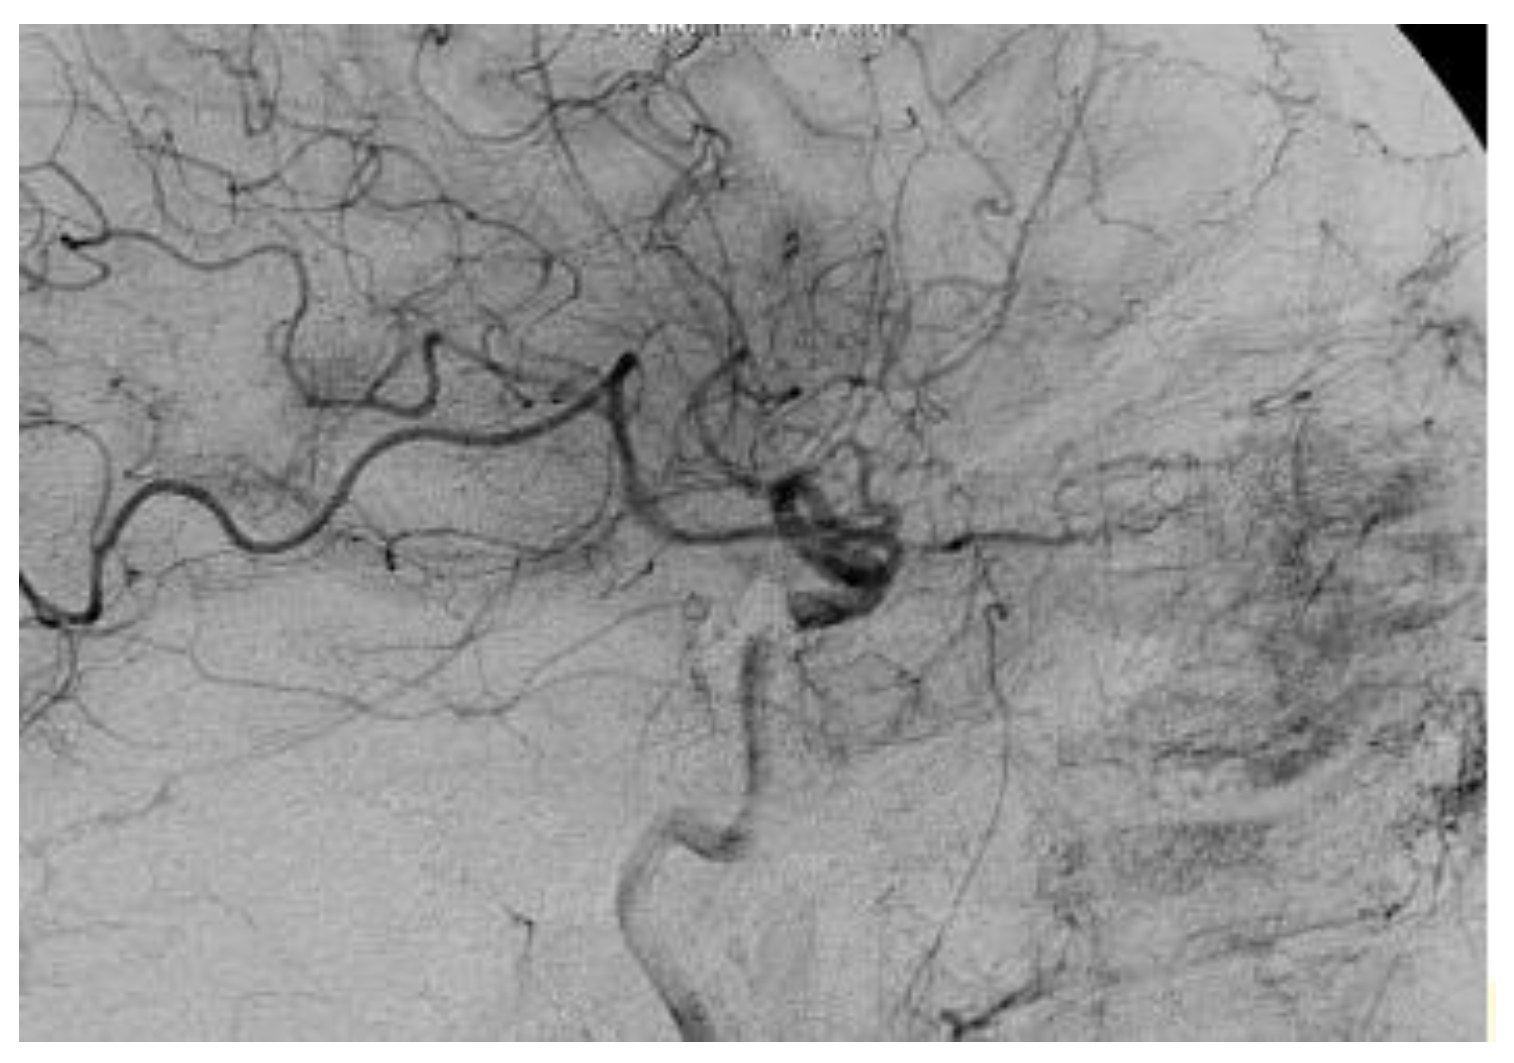

The multidisciplinary team involved in this case comprised neurosurgeons and interventional neuroradiologists. The treatment decided was carried out two times; the first provided the insertion of a cannula needle in the right orbital vein by a trans-palpebral anterior approach, while the second provided for the embolization of the cavernous sinus seat of the venous part of the fistula, through the placement of 5 spirals (Vortex 2x5, Boston), up to the complete exclusion of the fistula. The angiographic control performed immediately after the affixing of the spirals showed the complete normalization of the circulation between the internal and external carotid (Figure 6).

Figure 6. The selective cerebral angiography revealing a dural fistula of the right cavernous sinus.